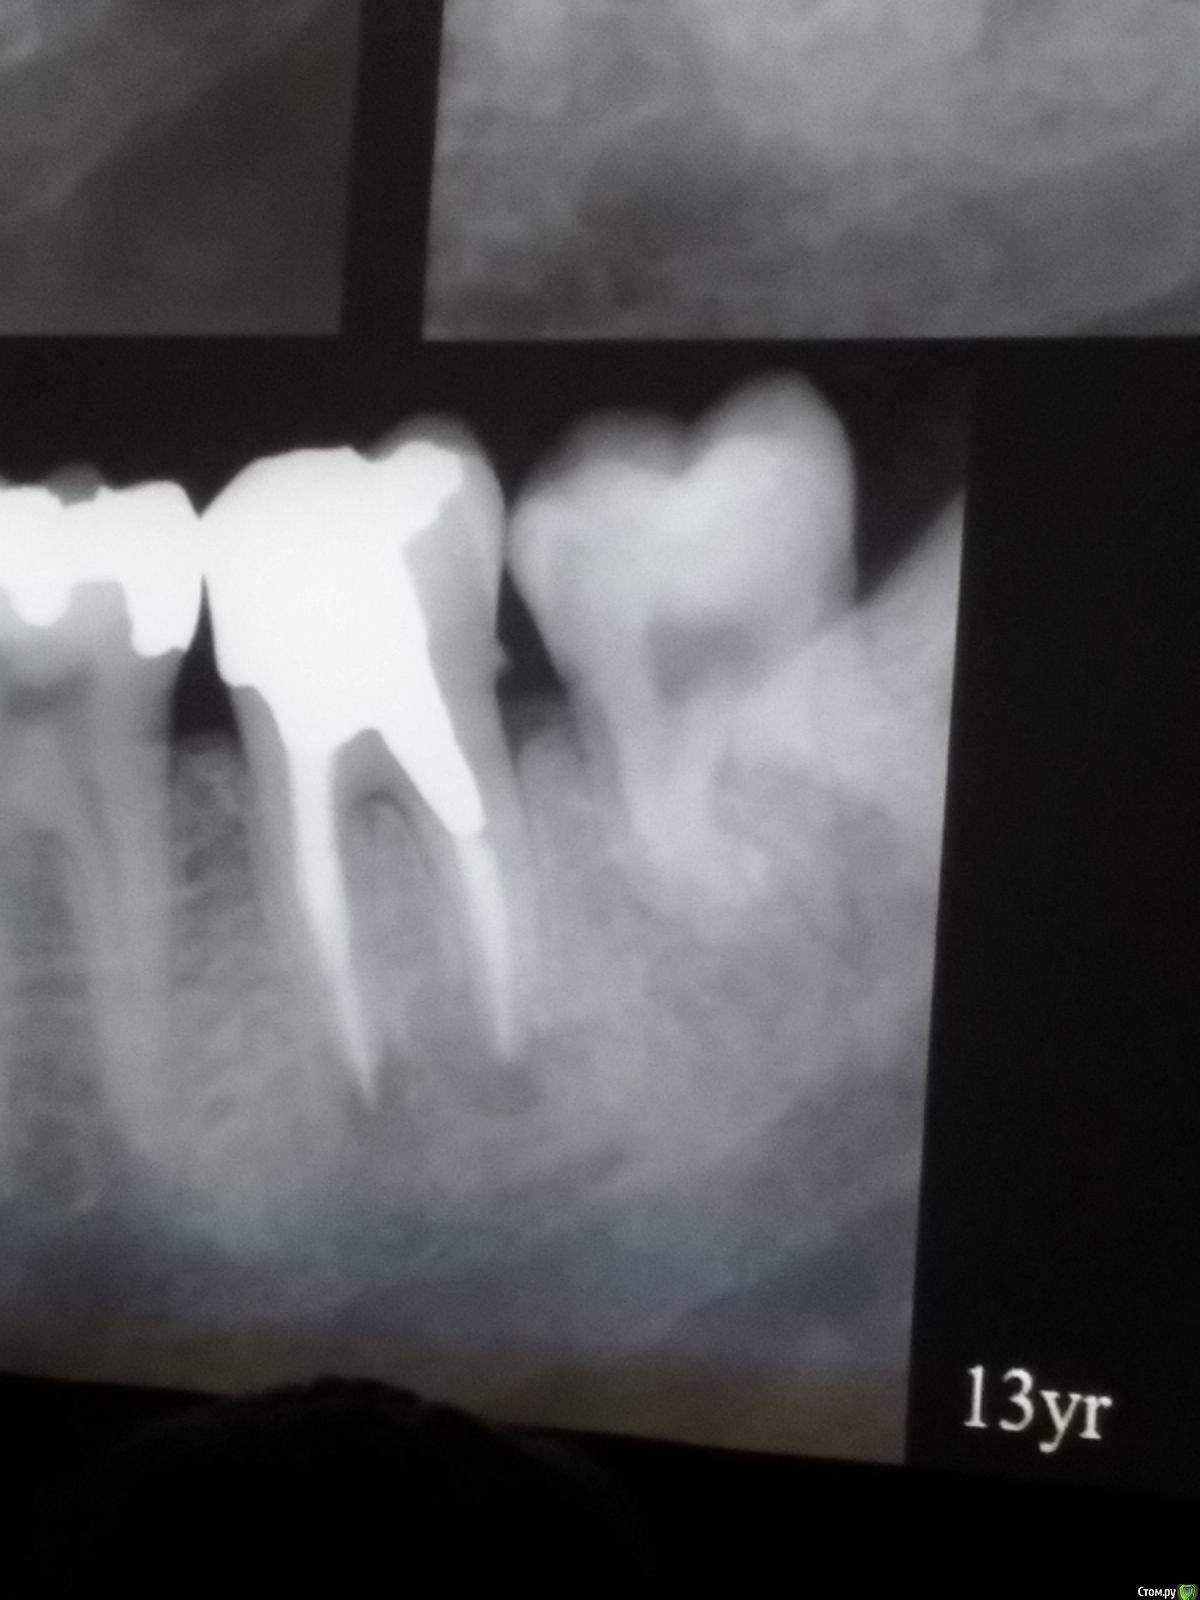

Популярный пост Kolchanov Опубликовано 11 марта, 2017 Популярный пост Поделиться Опубликовано 11 марта, 2017 (изменено) Товарищи, скажу я вам...........Вкратце. Может я где-то что-то и приврал, надеюсь, кто еще был, поправят. Честно говоря немного прибалдел от уровня Доктора. Очень, очень высоко! Приедет еще раз, пойду еще. 1) Фиссуры зондирует острым зондом и выпиливает все дотла. По факту у него уже пломбы, а не герметизация.2) Bite-wing у первичных пациентов всегда.3) Если кариес диагносцирован, то лечить его, пофиг какой он там. Эмали, дентина…4) Препарирует до твердого (или до вскрытия J ). CAD, СID… в топку. Кариес маркером не пользуется, проверяет острым зондом/экскаватором. Вычищает все дотла. Считает, что даже небольшое количество бактерий в дентине под пломбой вызывают хроническое воспаление в пульпе. С его слов у него на контроле где-то 500 вскрытий, не удивительно при таком подходе к очистке.5) Тщательная изоляция. Коффер порвался – меняет. Большое значение герметичности реставрации. под замену6) Критерии обратимости и необратимости.Гистологически, обратимый тот, что без абсцессов в пульпе, но клинически это понять нельзя, только предположить.Здесь был бы обратимый, если бы не удалил. Нет микробов в пульпе. Линия - граница обработки.Покрытие 27 лет назад. Dycal, СИЦ, композит. От дайкала одно воспоминание.7) Вскрылись. Размер перфорации, возраст и прочее не играют роли, важно только состояние пульпы, т.е. диагноз.Примеры перфораций.8) Кровотечение останавливает стерильным ватным шариком. Если останавливается, то покрытие, если нет, то пульпотомия или пульпэктомия.9) Использует гидроокись кальция (порошок), перекрывает Dycal или СИЦ. Потом восстановление Нередко под IRM, потом все убирает (через пару-тройку месяцев) и смотрит, что получилось. Порой приходится повторять! Использует и МТА, его тоже убирает.10) Наблюдение 6мес, 1 год, 2…. Все может провалиться и через месяц и через 24 года.Примеры проваловНиже - 24 года спустя появилась дуля. 11) Неравномерная облитерация полости зуба на RG (после покрытия) – признак текущего хронического воспаления, где-то остались микробы. Рекомендует эндо.12) Мостик который образуется – это не дентин! И одонтобласты не регенерируют и новые не образуются. Что это такое он и сам не знает, но раз это твердые ткани, то и наплевать.Вот фиолетовое это дентинные опилки вмурованные в розовую ткань бог знает кем сформированную.13) Пульпотомия в зубах с несформированной верхушкой и в сформированных, при подозрении на частичное поражение коронковой пульпы. Иссекается стерильным алмазным бором часть пульпы, гидроокись, временная пломба на 90 дней, после повторное раскрытие, оценка результата, восстановление в случае формирования твердых тканей. Гипохлоритом можно мыть, можно не мыть, если мыть, то 0,5-1%.14) В апикальной части пульпа чаще витальна, чем нет.15) Периапикальные поражения возникают по причине поступления токсинов микробов с током крови, а не самих бактерий.16) За апикальные расширения в полностью некротических случаях. Надо механически отодрать биопленку и срезать инфицированный дентин. На ирриганты надежды мало.17) Биопленка на поверхности в 6% случаев.Синенькие пид@расы18) Обработку проводить нежно, краун-даун. Чередовать с H-файлом, чтобы посмотреть докуда распространяется некроз.19) Патенси в витальных кейсах не колоть, сохранять витальную пульпу в констрикции!Формирование еще большего сужения в констрикции за счет сохранения витальной пульпы. Изменено 11 марта, 2017 пользователем Kolchanov 31 Ссылка на комментарий

Популярный пост Kolchanov Опубликовано 12 марта, 2017 Автор Популярный пост Поделиться Опубликовано 12 марта, 2017 Второй день.1) Дезинфекция зуба и раббер дама перед работой. Вначале установка системы, потом протирка тампоном 30% перекиси, потом протирка всего йодинолом. Потом преп, потом повторение и только потом доступ к к/к. Все старые реставрации надо убрать, кариес убрать, противник лечения через коронку.2) Гидроокись на неделю. Замешивает на стерильном физрастворе. При необходимости повторяет. Т.е. в случае сохранения свища, симптоматики, экссудации, запаха. Если свищ не исчезает после трех смен временных вложений, то хирургия.3) Пломбирует латеральной компакцией. Лучше контроль длины обтурации.4) Высушивание канала стерильными штифтами, на рабочую длину минус 1мм. После высушивания штифт оставляется на 60с. в канале и должен выйти сухим.5) Определение рабочей длины. Витальные случаи. АЛ должен три раза дать одну и ту же картинку в определенной точке + проверка RG. Девитальные случаи. На АЛ полагаться сложно, т.к. из-за наличия резорбции констрикции может врать, больше ориентируется на RG.6) Использует ЦОЭ силеры. Резорбируются при незначительном выведении. Резорбируются в канале, позволяя закрыть апекс цементоподобной тканью. Вот так вот.Случаи исчезновения силера, как за пределами канала так и в канале7) Выведение материала (не важно какого) в большом объеме способно вызвать защитную реакцию тканей. Которая должна пройти спустя некоторое время. (иногда это будет 25 лет J Случай 1ый. Студенты наломали инструментов. Периодонтит на RG через год. Резекция и гистология. Бактерий не обнаружил. Да, маленькое замечание. Каждый препарат дает 500-600 срезов. И ищет он на всех. Объем работы, конечно….Случай 2й. Его собственный. Периапикальное поражение, обнаруженное на реколле через 10 лет зажило еще через 15.8) «Функционирующий зуб» считает результатом неприемлемым. Осталась инфекция с которой надо что-то делать. То, что бактерий можно замуровать в дентинных трубочках и под пломбировочным материалом, считает неправильным. Продукты метаболизма один фиг будут просачиваться и могут поддерживать реакцию воспалительную.Случай. Синее – маленькая кучка микробов, предположительно, препятствовавших заживлению очага.9) Биопленка на поверхности корня может принимать вид кальцификатов (камней) и тут уже только хирургия в помощь. При длительном существовании свищевого хода, например.Черное - это камни вокруг апикального отверстия. И гистология их с кучей синих микробов.Здесь камни на фуркации и отсутствие заживления и свищ даже после ретроградной обработки и пломбировки.А здесь вообще чертова уйма камней. И зацените разветвление канала в этом боковом резце (последнее фото препарата). 10) Реваскуляризация.В некротических случаях дентина не образуется, т.к. одонтобластов нет и не будет новых. Образуется та самая бог знает какая ткань, которая даже и с корнем не связана может быть. Суть здоровый дентикль-петрификат. А в витальных это не реваскуляризация, а обычное формирование корня. Так что нечего тут.11) Трещины дентина.Советует расшивать, братья и сестры. Без фанатизма, если нет симптоматики, но, по возможности максимально. Если есть симптоматика, то там уже по обстоятельствам. Чертова уйма микробов там и ползет, ползет к пульпе. Надеюсь, что еще раз этот замечательный Доктор приедет. Схожу с удовольствием. 2 23 Ссылка на комментарий